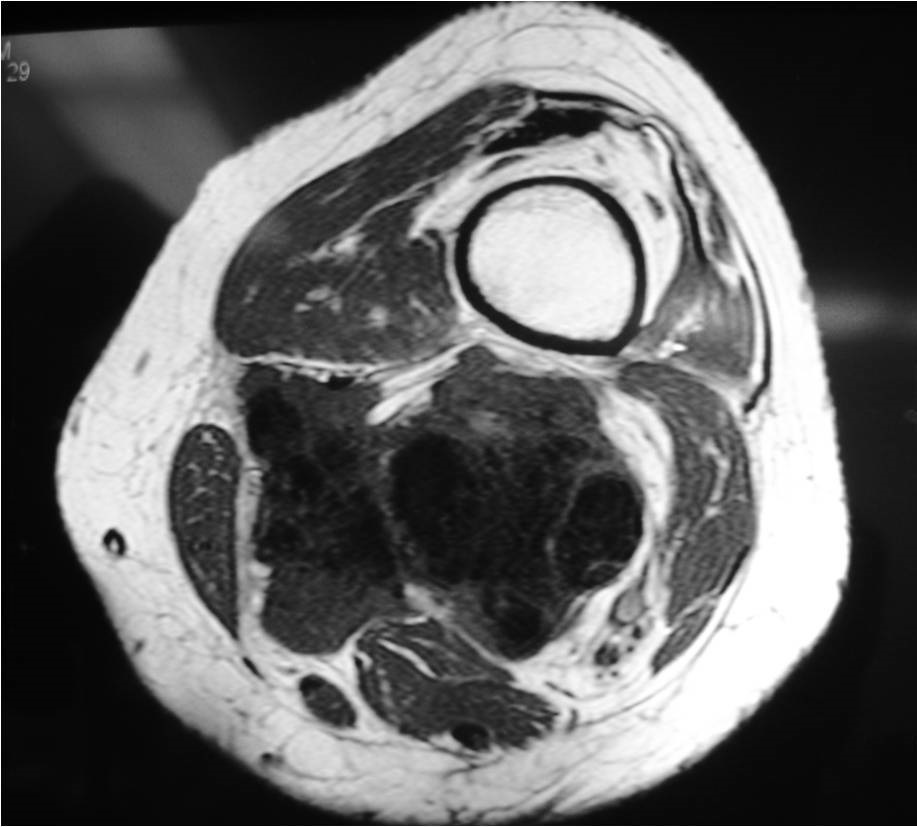

On radiographs, extraskeletal osteosarcomas show a mass with soft tissue density and variable amounts of mineralization best visualize on an Xray or CT scan, which may appear as a dense, cloudlike area (Fig. 1-3). A well circumscribe heterogeneous mass, Isointense to muscle on T1-weighted images and isointense to mildly hyperintense on T2-weighted images (Fig. 4-7). Mineralized areas will be dark on T1 and T2 weighted images.

Fig. 4 & 5: MRI of an Extraskeletal Osteosarcoma Axial (Fig. 4) and sagital (Fig. 5) T1-weighted MR image of an extraskeletal osteosarcoma demonstrates an isointense signal with muscle in the posterior compartment of the thigh. Neurovascular structures seem to be invaded by tumor.